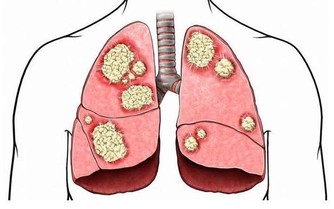

***2.脾胃、腸胃不好***

凡是有消化不良的人是脾胃虛弱引起的,可能是多吃了一點東西都消化不了,長期的蓄積在那;還有萎縮性胃炎、急性胃腸炎以及食積,肝胃鬱熱,這些都是因為消化不了引起的口臭。腸胃還有一種很常見的疾病引起的口臭那就是便秘了。腸道內堆積了大量的毒素、廢物,排不出去,就在裡邊蓄積。中醫講這叫濁氣上逆。這就很形像地從胃腸道的垃圾毒素臭氣往上走了,口氣就非常明顯了。